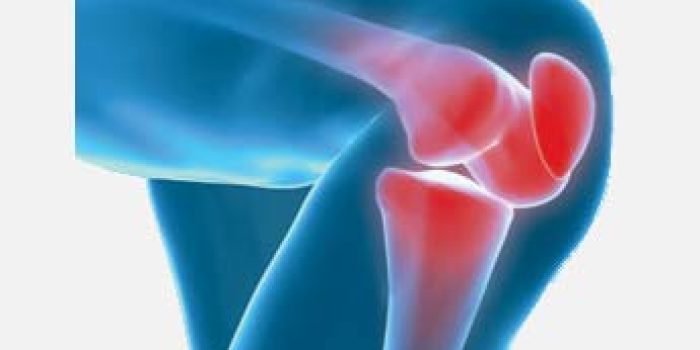

زانودرد بیشتر مواقع در اثر استفاده بیش از حد از مفصل زانو، کم تحرکی، گرم و سرد نکردن بدن موقع ورزش یا کشش نامناسب بدن بروز میکند. چاقی هم یکی از علل اصلی زانودرد است.

افزایش وزن نیز یکی از علل درد زانو میباشد. تحقیقات نشان داده است که به ازای هر نیم کیلوگرم وزن اضافی، فشار وارده بر مفصل زانو به میزان ۵ برابر آن (۵/۲ کیلو) زیاد خواهد شد. در نتیجه سعی کنید وزن خود را در حد طبیعی و نرمال حفظ کنید تا دچار درد زانو نگردید.